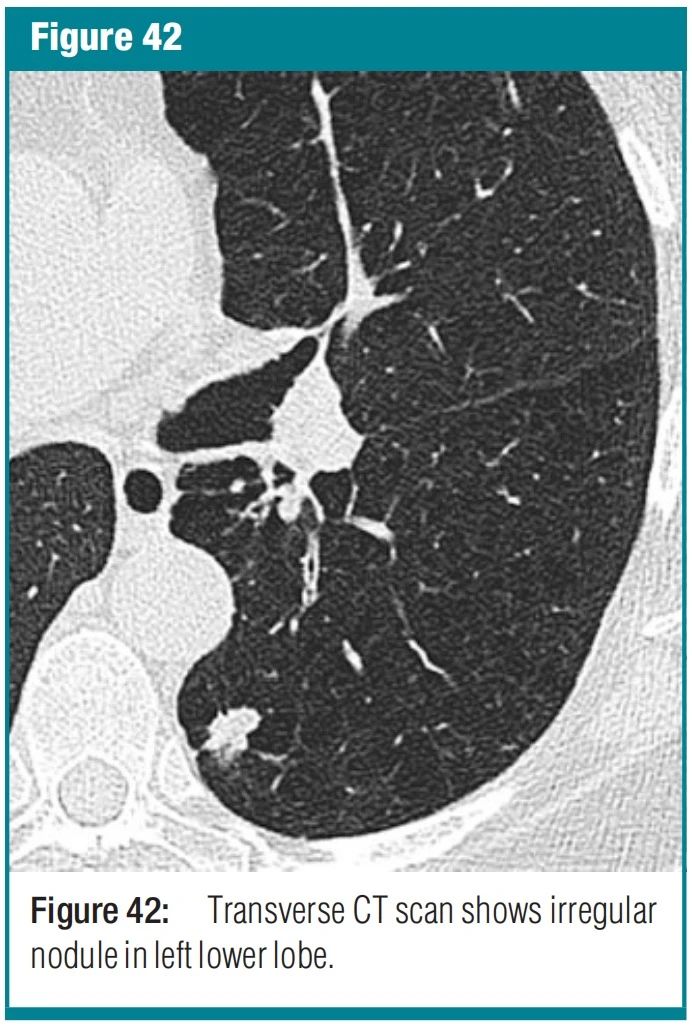

1c82f403ee551d08e7feccdb76ed044a.jpg 图3 nodule-结节 X 线和 CT 扫描-胸部 X 线检查显示结节呈圆形不透明,边界清晰或模糊,直径可达 3 厘米。(a) 腺泡结节为圆形或者卵圆形,边界不清,直径5~10mm,一般认为是实变导致腺泡实变造成的。本用法只适用于多发病灶时。(b) 假结节可以可以类似肺结节,可能是肋骨骨折,皮肤病变,体表的设备,解剖变异或者重叠影。在CT上,结节表现为圆形或者不规则的密度增高影,边界清楚或者不清楚。(a) 小叶中心结节与胸膜表面、裂隙和小叶间隔相距数毫米。它们可能是软组织或毛玻璃衰减的。小叶中心结节的大小从几毫米到一厘米不等,通常边界不清。(b) 微结节的直径小于 3 毫米。(c) 毛玻璃结节(同义词,非实性结节)表现为肺部模糊的衰减增加,但不会消除支气管和血管边缘。(d) 实性结节具有均匀的软组织衰减。(e) 部分实性结节(同义词,半实性结节)由毛玻璃和实性软组织衰减成分组成。